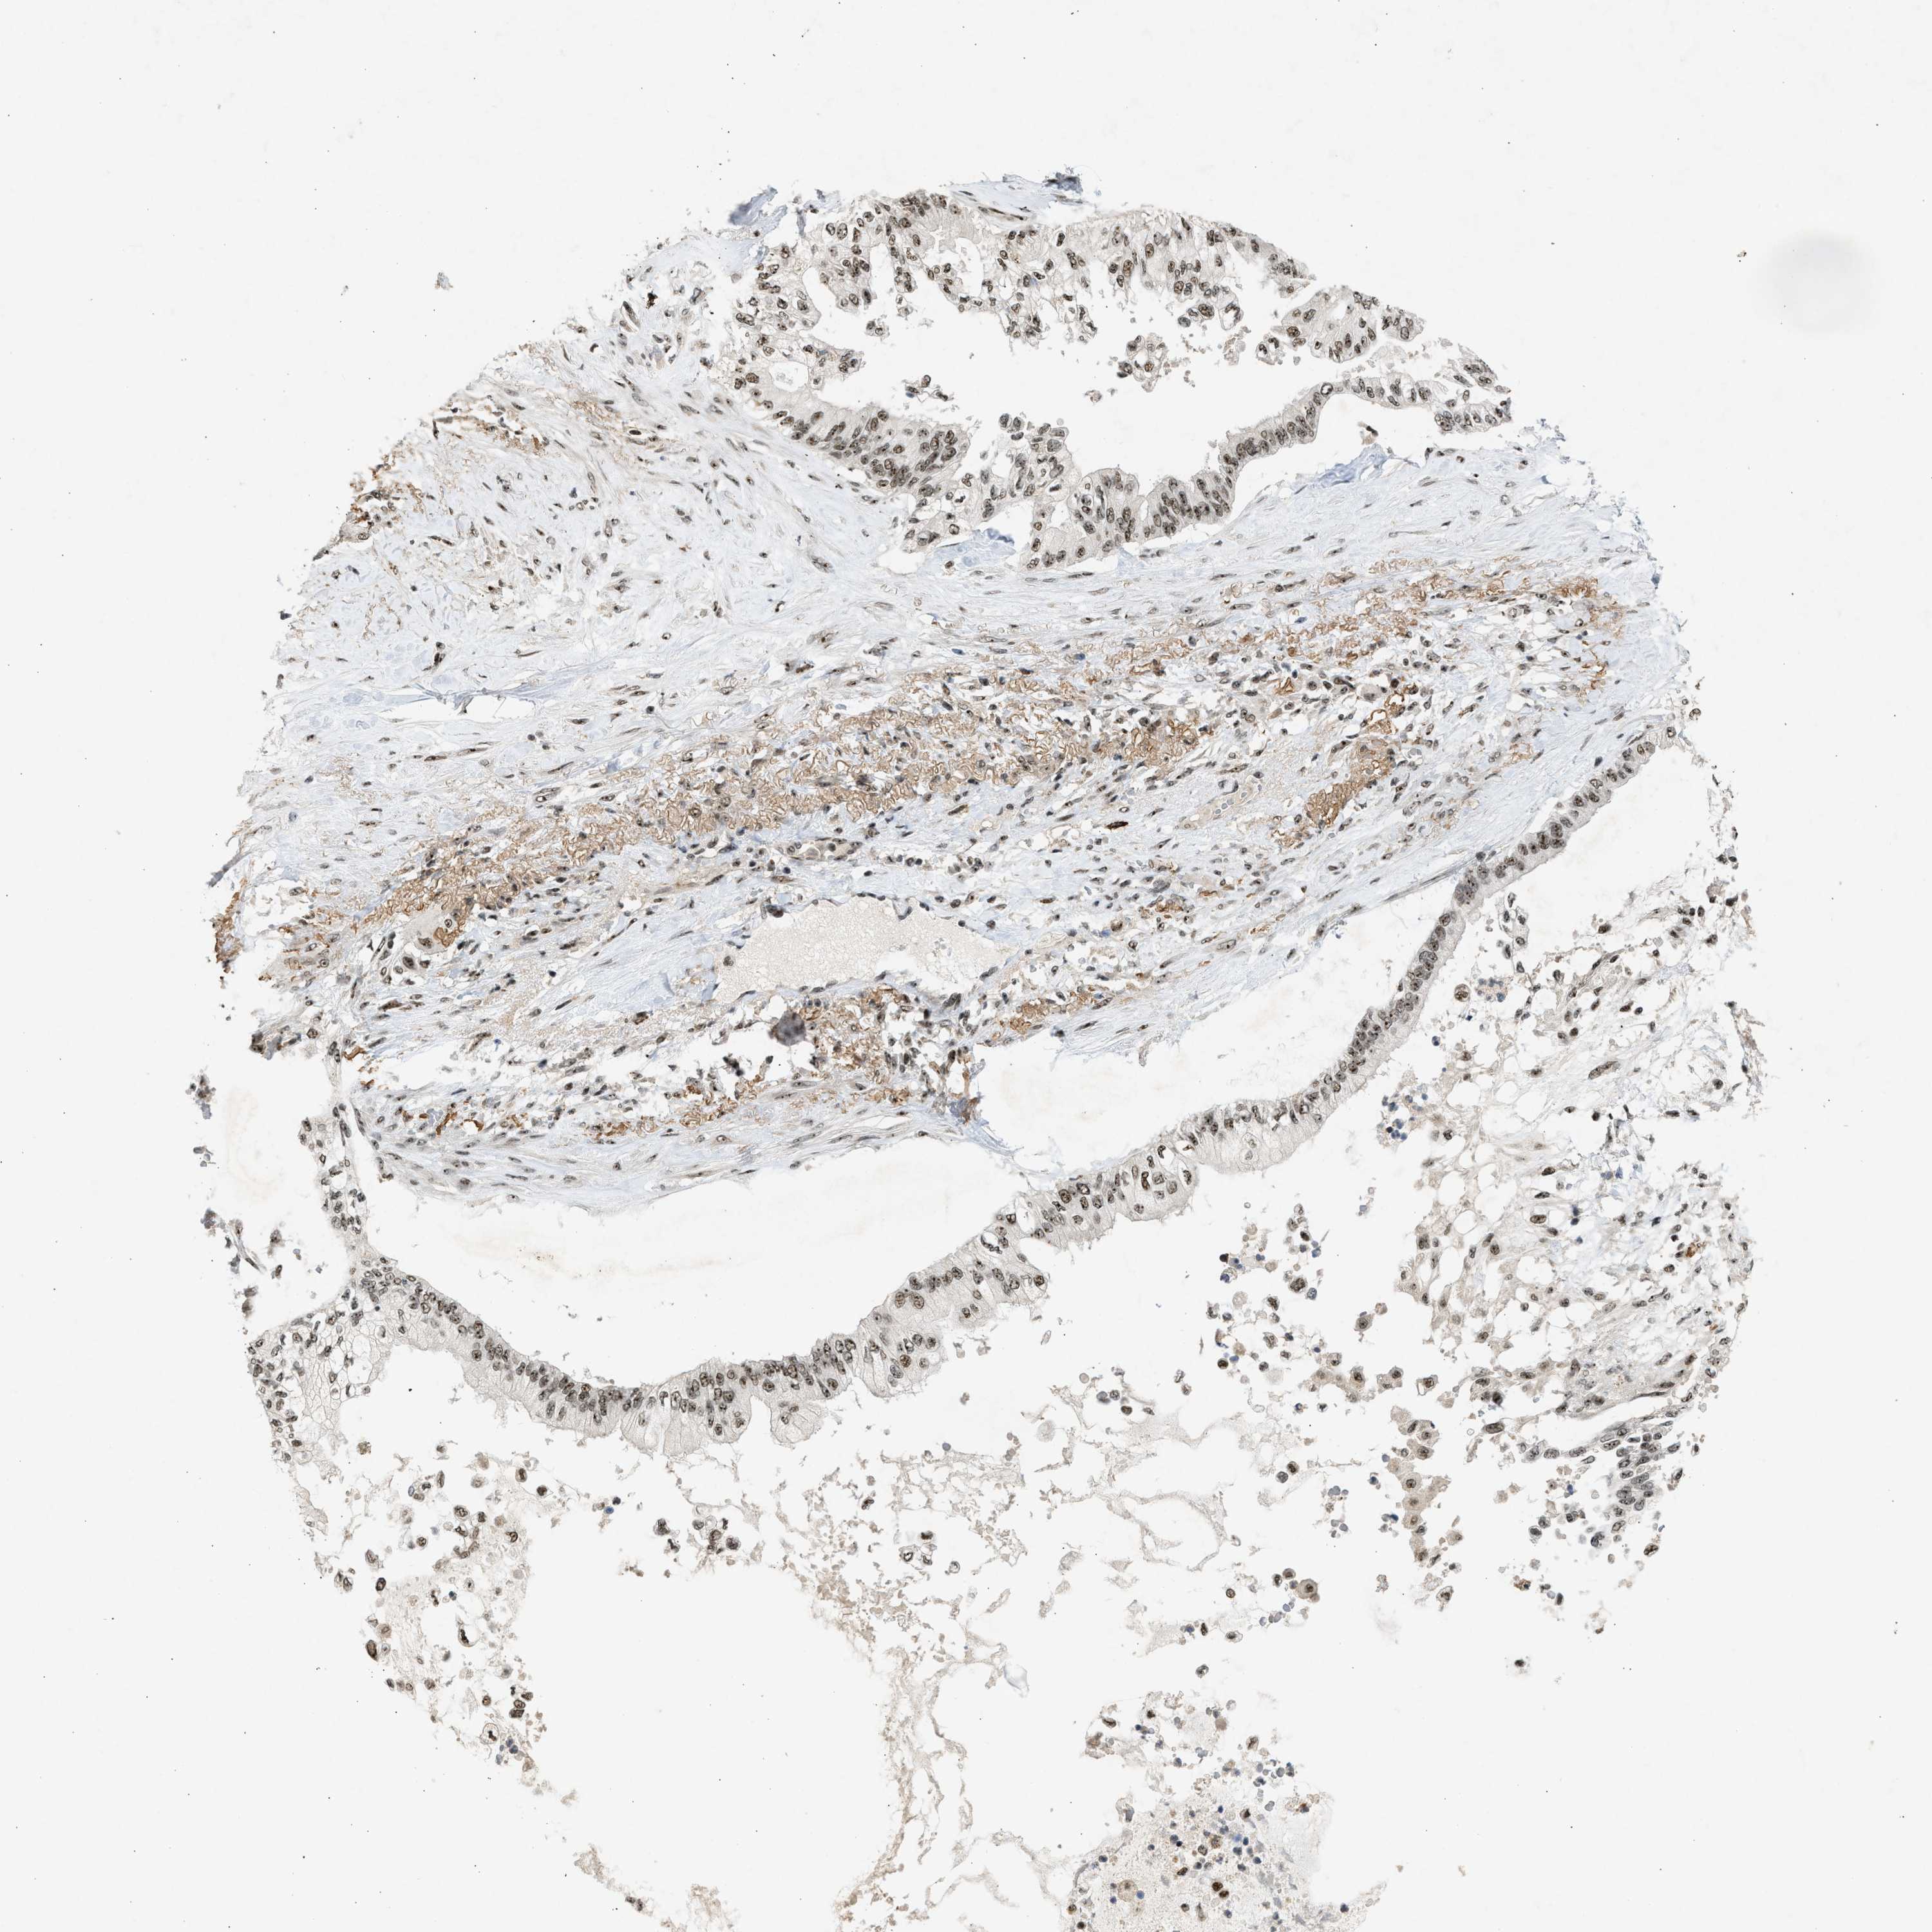

PANCREATIC CANCER - Protein expressioni

A mouse-over function shows sample information and annotation data. Click on an image to view it in a full screen mode. Samples can be filtered based on level of antibody staining by selecting one or several of the following categories: high, medium, low and not detected. The assay and annotation is described here.

Note that samples used for immunohistochemistry by the Human Protein Atlas do not correspond to samples in the TCGA dataset.

Antibody stainingi

Antibody staining in the annotated cell types in the current human tissue is reported as not detected, low, medium, or high, based on conventional immunohistochemistry profiling in selected tissues. This score is based on the combination of the staining intensity and fraction of stained cells.

Each image is clickable and will lead to virtual microscopy that enables deeper exploration of all samples and also displays staining intensity scores, fraction scores and subcellular localization as well as patient and tissue information for each sample.

Antibody CAB018396

Staining

High

Medium

Low

Not detected

Intensity

Strong

Moderate

Weak

Negative

Quantity

>75%

75%-25%

<25%

None

Location

Nuclear

Cytoplasmic/membranous

Cytoplasmic/membranous,nuclear

Adenocarcinoma, NOS